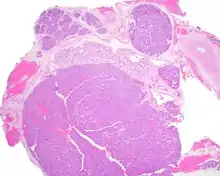

Canalicular adenoma growths are usually small at the time they are noticed, with an average size of about 1.6 cm.[1] Their histologic appearance is very distinct, with a channel-like pattern between cords and ribbons; the pattern has been described as resembling a "string of pearls."

The growths often contain are often small bight squamous balls, or morules. They also tyipcally contain a well-developed supporting tissue - a fibrous stroma - which is rich in hyaluronic acid and chondroitin sulphate.[1] In a few cases, the growths may contain small calcium deposits or microliths. Although it is seldom necessary, a pathologist can confirm the existence of canalicular adenoma through immunohistochemistry studies, with the cells reacting with pancytokeratin, S100 protein and SOX10, with a delicate GFAP reaction around the periphery.[5][1][6][7] Although it is a benign tumor, a positive diagnosis of canalicular adenoma may be necessary to exclude the existence of other medical conditions such as a basal cell adenoma, pleomorphic adenoma, adenoid cystic carcinoma, and polymorphous adenocarcinoma.